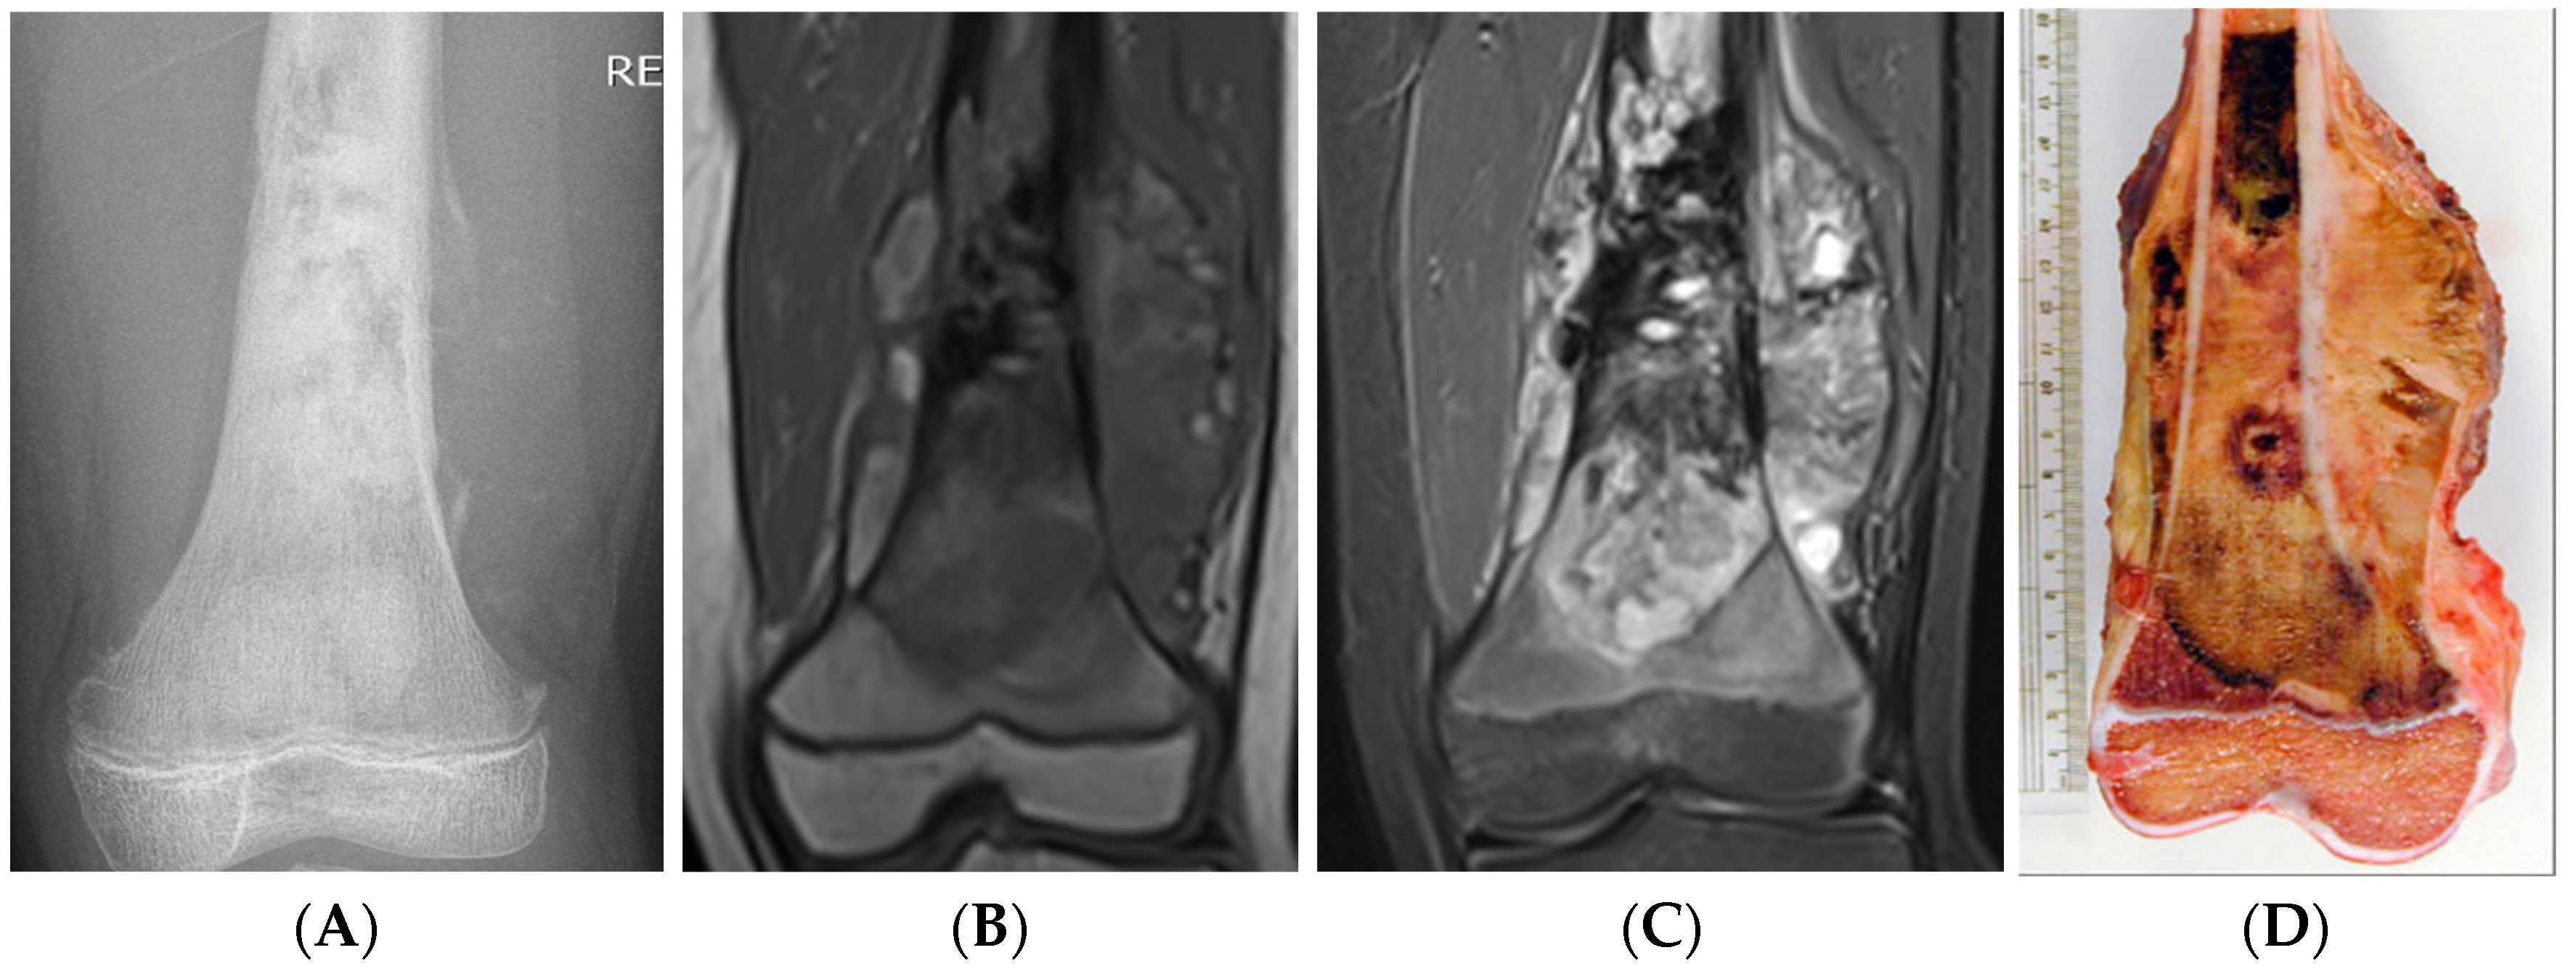

6.1. Osteosarcoma